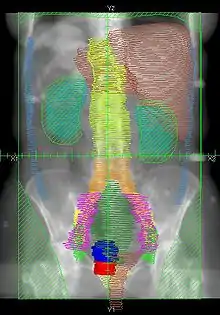

![]() |

Example of a PA whole abdomen/pelvis radiation therapy treatment field used at Tufts/Brown residency program. Actual patient contours should guide field design.